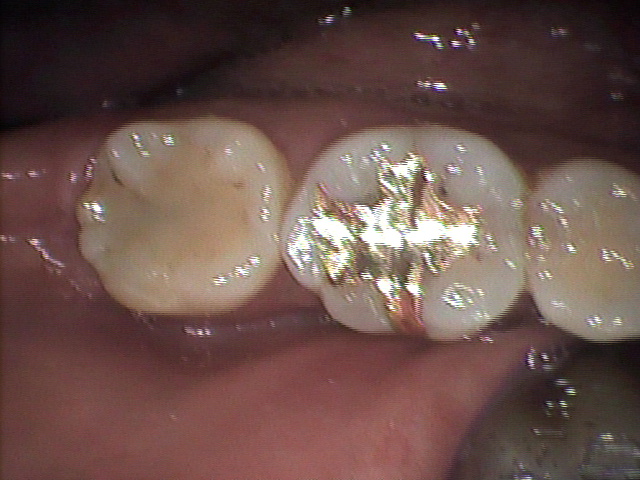

3―4.金インレー除去後の「むし歯」の状態

金インレー除去後、CCD画像支援装置により病巣部を拡大すると「むし歯」のコロニーを確認(矢印)することができます。画像精査の結果、充填物の辺縁封鎖が十分におこなわれており、接着剤の付着状況ならびにコロニーの分布状態から、この「むし歯」の原因は外部からの感染ではなく形成時の残存細菌によるもの、と考えられます。(Photo-6.)